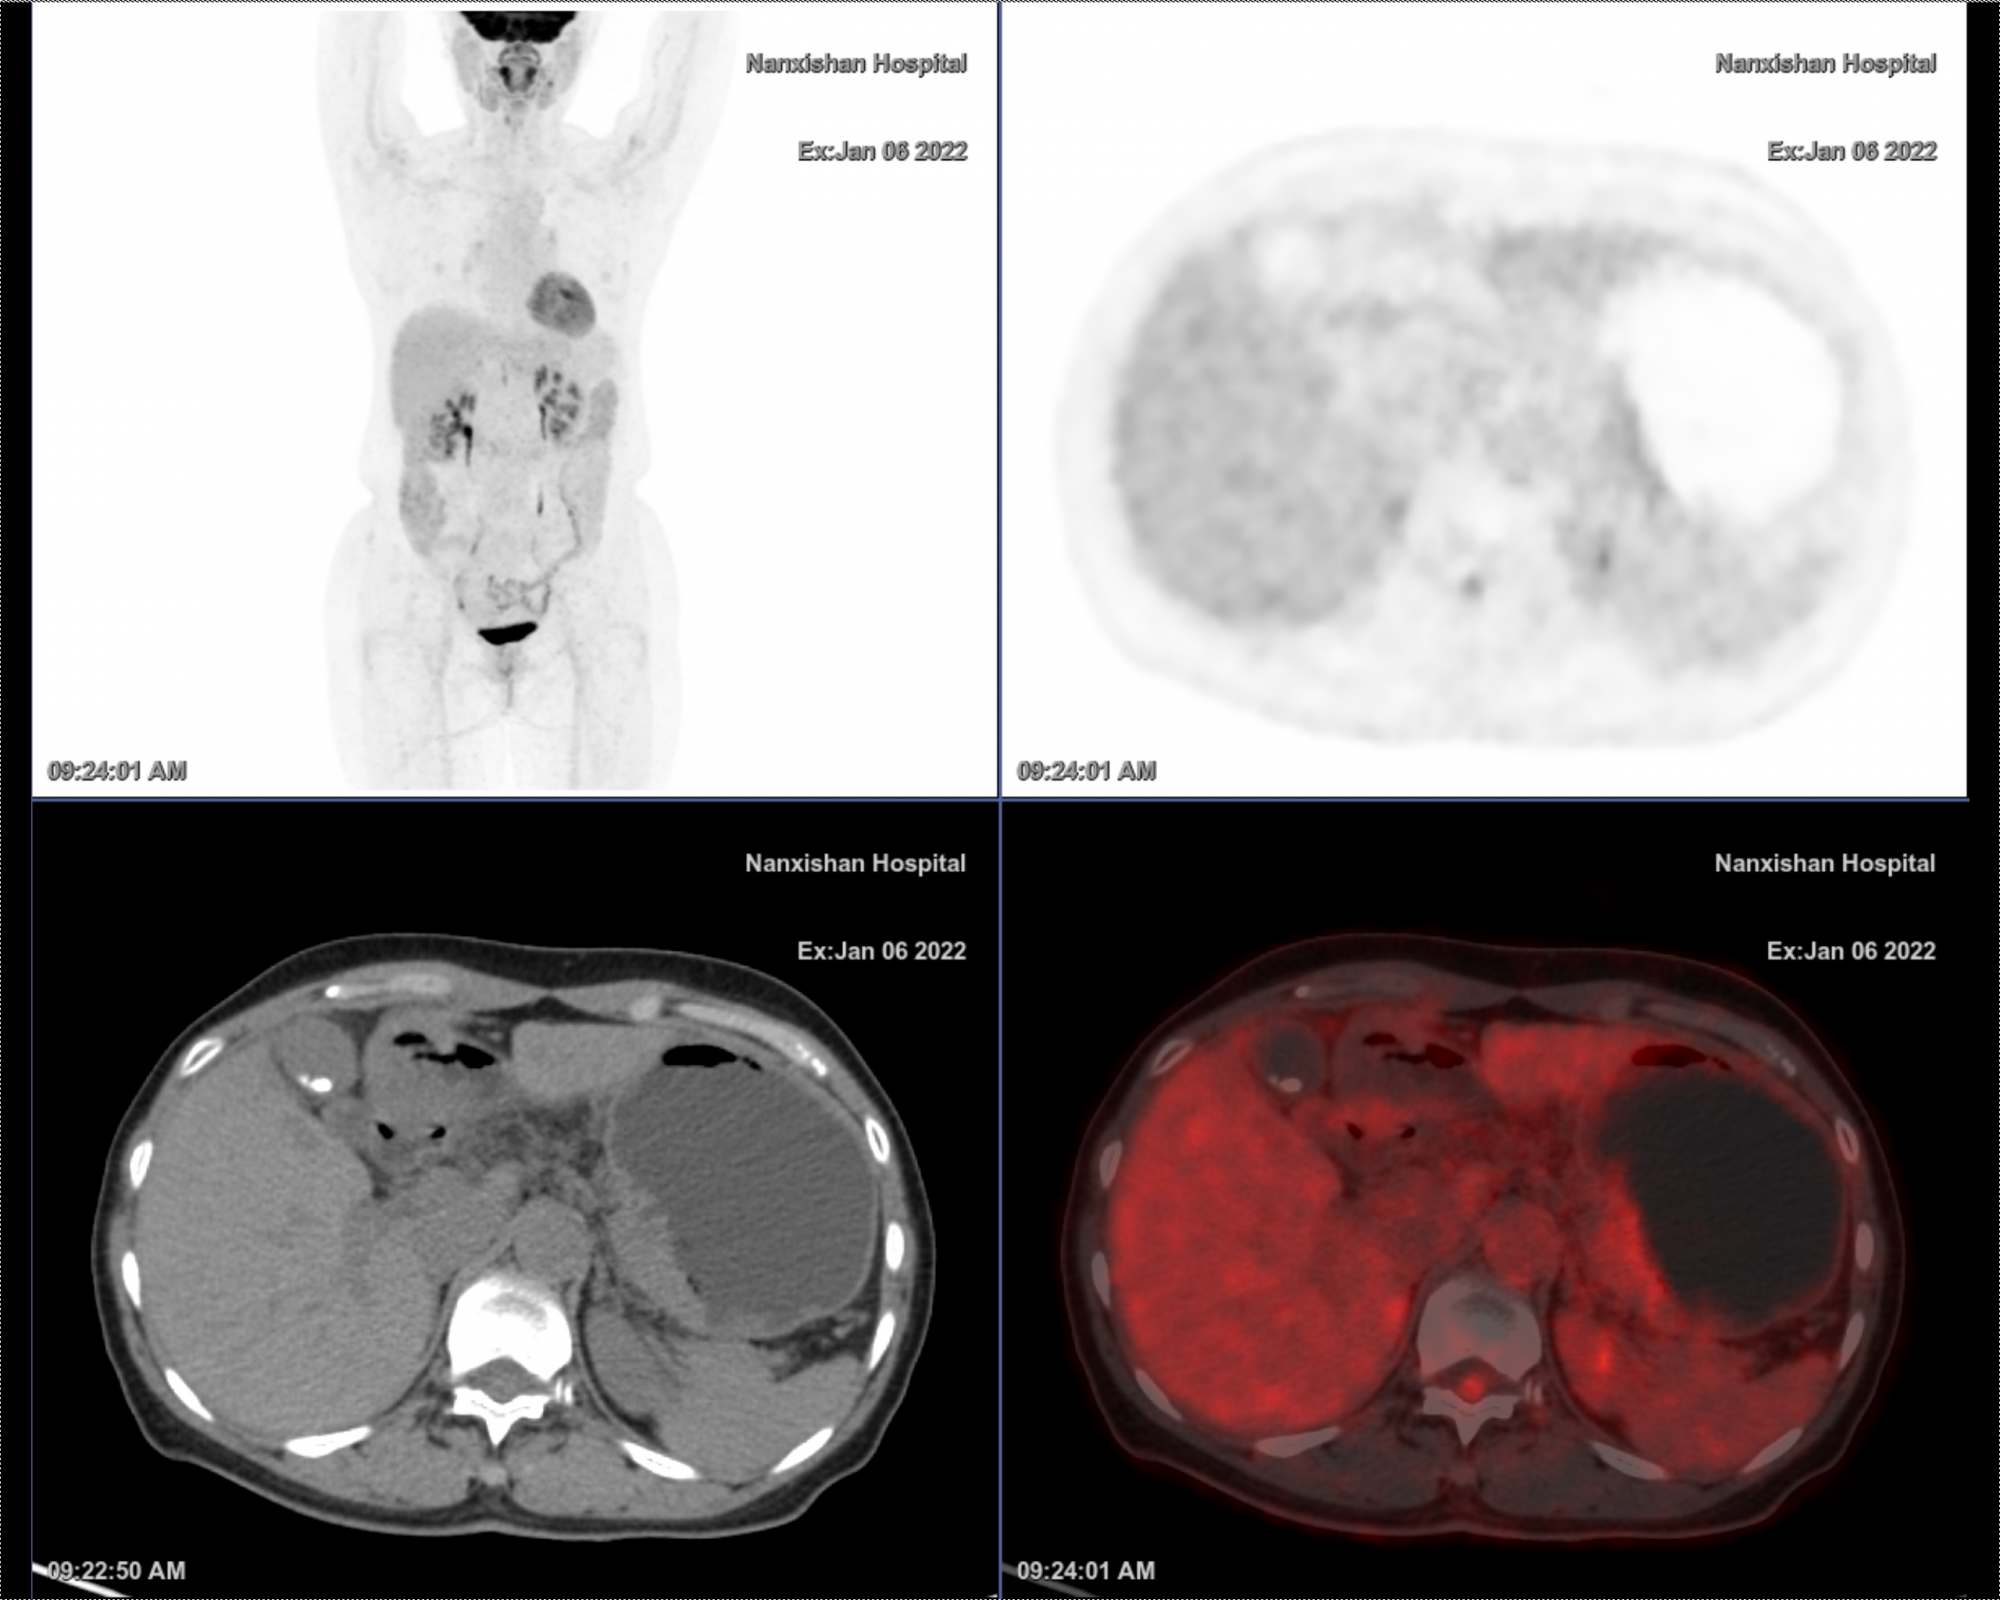

PET CT诊断:胃小弯近贲门处胃壁不规则增厚,代谢增高,建议胃镜活检

图A为全身PET MIP图,图B为PET断层图,图C为CT图,图D为PET CT融合图

经PET/CT检查后显示,真凶”终于找到了,是胃体底的低分化腺癌,属于典型的胃癌小病灶大转移。据了解,胃癌小病灶大转移通常发生在低分化腺癌。恶性程度高,通常病灶很小的时,就有转移灶了。甚至还有原发灶已经切除的情况下,转移灶依然长起来了情况。低分化腺癌即使没有转移,病灶切除了病灶,仍不能掉以轻心,仍然要重视起来。

南溪山医院核医学科主任黎川华介绍,PET/CT在肿瘤中的应用较其他的影像学方法有明显的优势。王阿姨是典型的小病灶大转移病例,病灶隐匿,较难发现,正是有赖于该院目前最先进的全息数字超级迭代PET/CT以及科室医疗团队的诊疗能力才能查找“真凶”。她表示,PET/CT显像灵敏度比较高,除了能够更早的判断肿瘤的大小及转移灶的大小,还能评价肿瘤经过治疗后原发肿瘤有无缩小,淋巴结转移有无减少,远处转移是否被控制,重要的是提供肿瘤的活性,对预后判断及下一步治疗计划起到非常重要的意义。